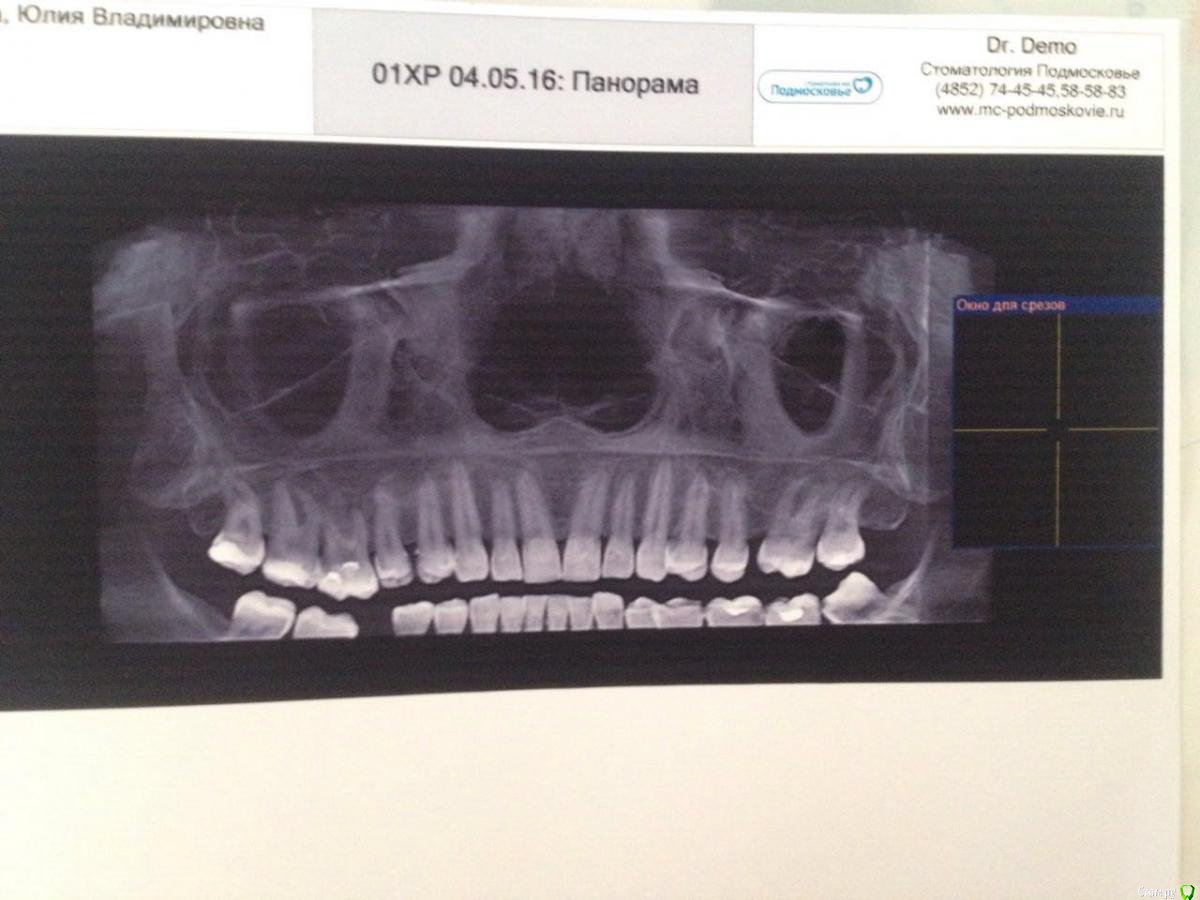

Julsvs Опубликовано 12 мая, 2016 Автор Поделиться Опубликовано 12 мая, 2016 Продолжение истории. Проверки зуба на витальность не нашла- в Ярославле это не делают. Но сделала КТ стоматологическое.С этим КТ была у стоматолога- терапевта: сказвла, что можно полечить, и на снимке ей кажется, что есть киста. Отправили к стоматологу - хирургу. Молодая девушка, смотрела снимок КТ прямо послойно на компьютере, убеждает меня не трогать этот зуб, что есть небольшой парадонтит, но он не может быть причиной гайморита. Пошла в областную клиническую больницу, в ЧЛХ, хирург, зав отделением( отзывы о нем оочень хорошие, врач от бога), тоже особо не увидел ничего в этом зубе, но методом исключения, все таки пригли к мнению, что этот зуб может быть причиной. Так как остальные зубы все живые, а этот мертвый, и запломбирован( могу неправильно назвать) формальдегидным способом 20 лет назад, и что зуб сверху запечатан, а под пломбой может давать инфекцию внутрь. Спросила: может перепломбировать его? Сказал: а зачем? Не держитесь за него, все равно он мертв. Назначил удаление зуба в стационаре с ушиванием лунки. Сам зуб не болит, правда после промывания катетером пазухи, часа два ноет.И вот кому верить? Удалять или не удалять его? Может переличить? Может парадонтит вылечить? Зуб не жалко, жалко обтачивать здоровые зубы под мост, а имплант ЛОР не советует . Ссылка на комментарий

Julsvs Опубликовано 13 мая, 2016 Автор Поделиться Опубликовано 13 мая, 2016 Вот КТ( проблема в правой шестерке). Другого снимка нет- выдали результаты на диске. Ссылка на комментарий

Doctor Vlad Опубликовано 13 мая, 2016 Поделиться Опубликовано 13 мая, 2016 это снова опг получилось. окно в программе наведите на 16 15 зубы и срезы тоже выложите 1 Ссылка на комментарий

DmitrySH Опубликовано 13 мая, 2016 Поделиться Опубликовано 13 мая, 2016 Мелковат снимок. Да, там есть изменения вокруг шестерки. Может на КТ там что-то еще можно увидеть. Но если судить по этому снимку, то зуб подлежит эндодонтическому лечению. Для удаления сейчас нет поводов. 1 Ссылка на комментарий

Doctor Vlad Опубликовано 14 мая, 2016 Поделиться Опубликовано 14 мая, 2016 вижу периодонтит! пародонтита не вижу 1 Ссылка на комментарий

DmitrySH Опубликовано 27 мая, 2016 Поделиться Опубликовано 27 мая, 2016 На последнем снимке у 7 зуба хорошо видны щечные корни, вот сделайте тоже самое у 6-го Ссылка на комментарий